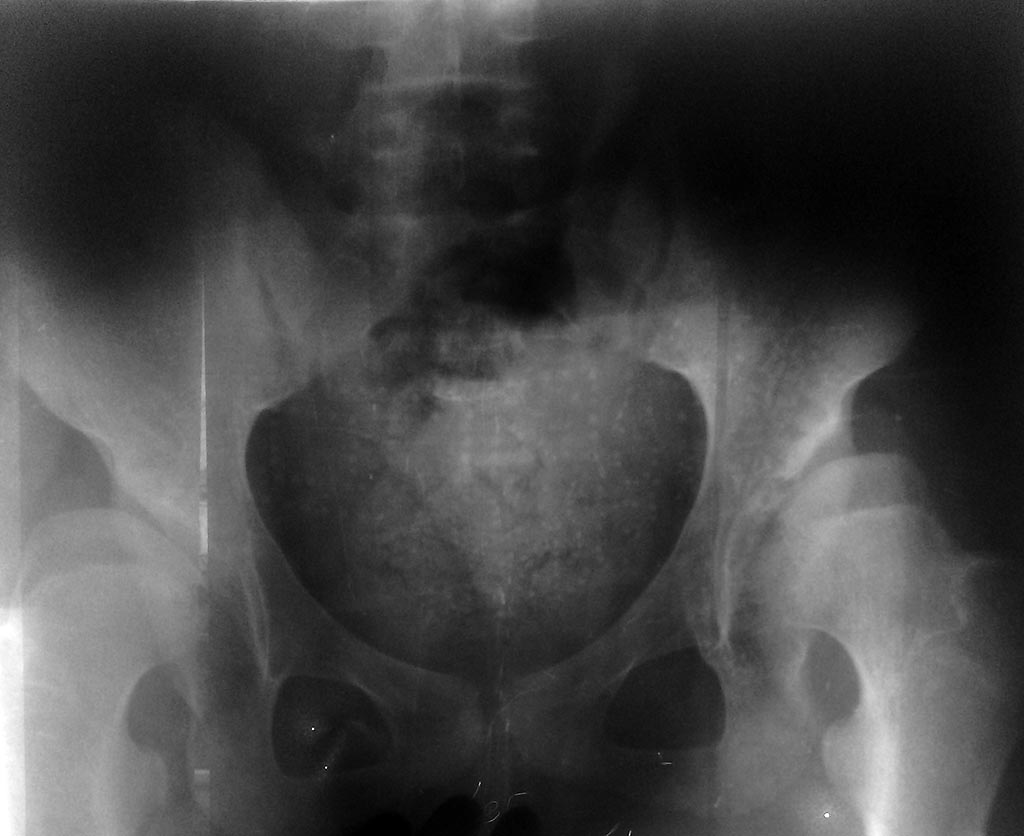

Здравствуйте,многоуважаемые коллеги, у нас такой случай: Больная М. 13 лет.

Лечилась консервативно с диагнозом "Врожденный двухсторонный вывих

бедра" На данный момент отмечается( смотрите на рентгенограмму)

латеропозиция (половина головки бедра находится вне вертлужной впадини)

недоразвитие вертлужных впадин, клинически - контрактура небольшом

обёме, редкие боли.Что вы посоветуете.